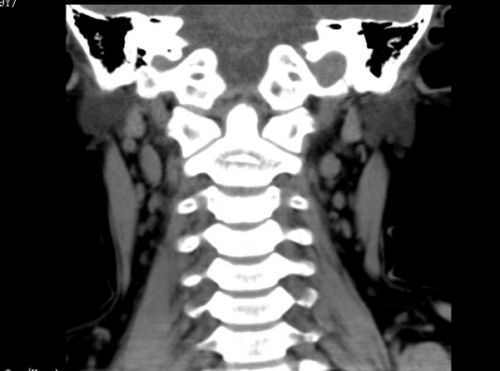

因为寰枢关节半脱位,彬彬每天都要接受牵引治疗。

经过治疗,彬彬的寰枢关节基本恢复正常。

目前,临床上对于寰枢关节半脱位的治疗主要以保守治疗为主,通过颈部牵引、局部理疗等缓解患者症状,并通过佩戴颈托修复患者关节囊和韧带,帮助患者治疗疾病。此后,则需要做功能锻炼逐步改善异常。